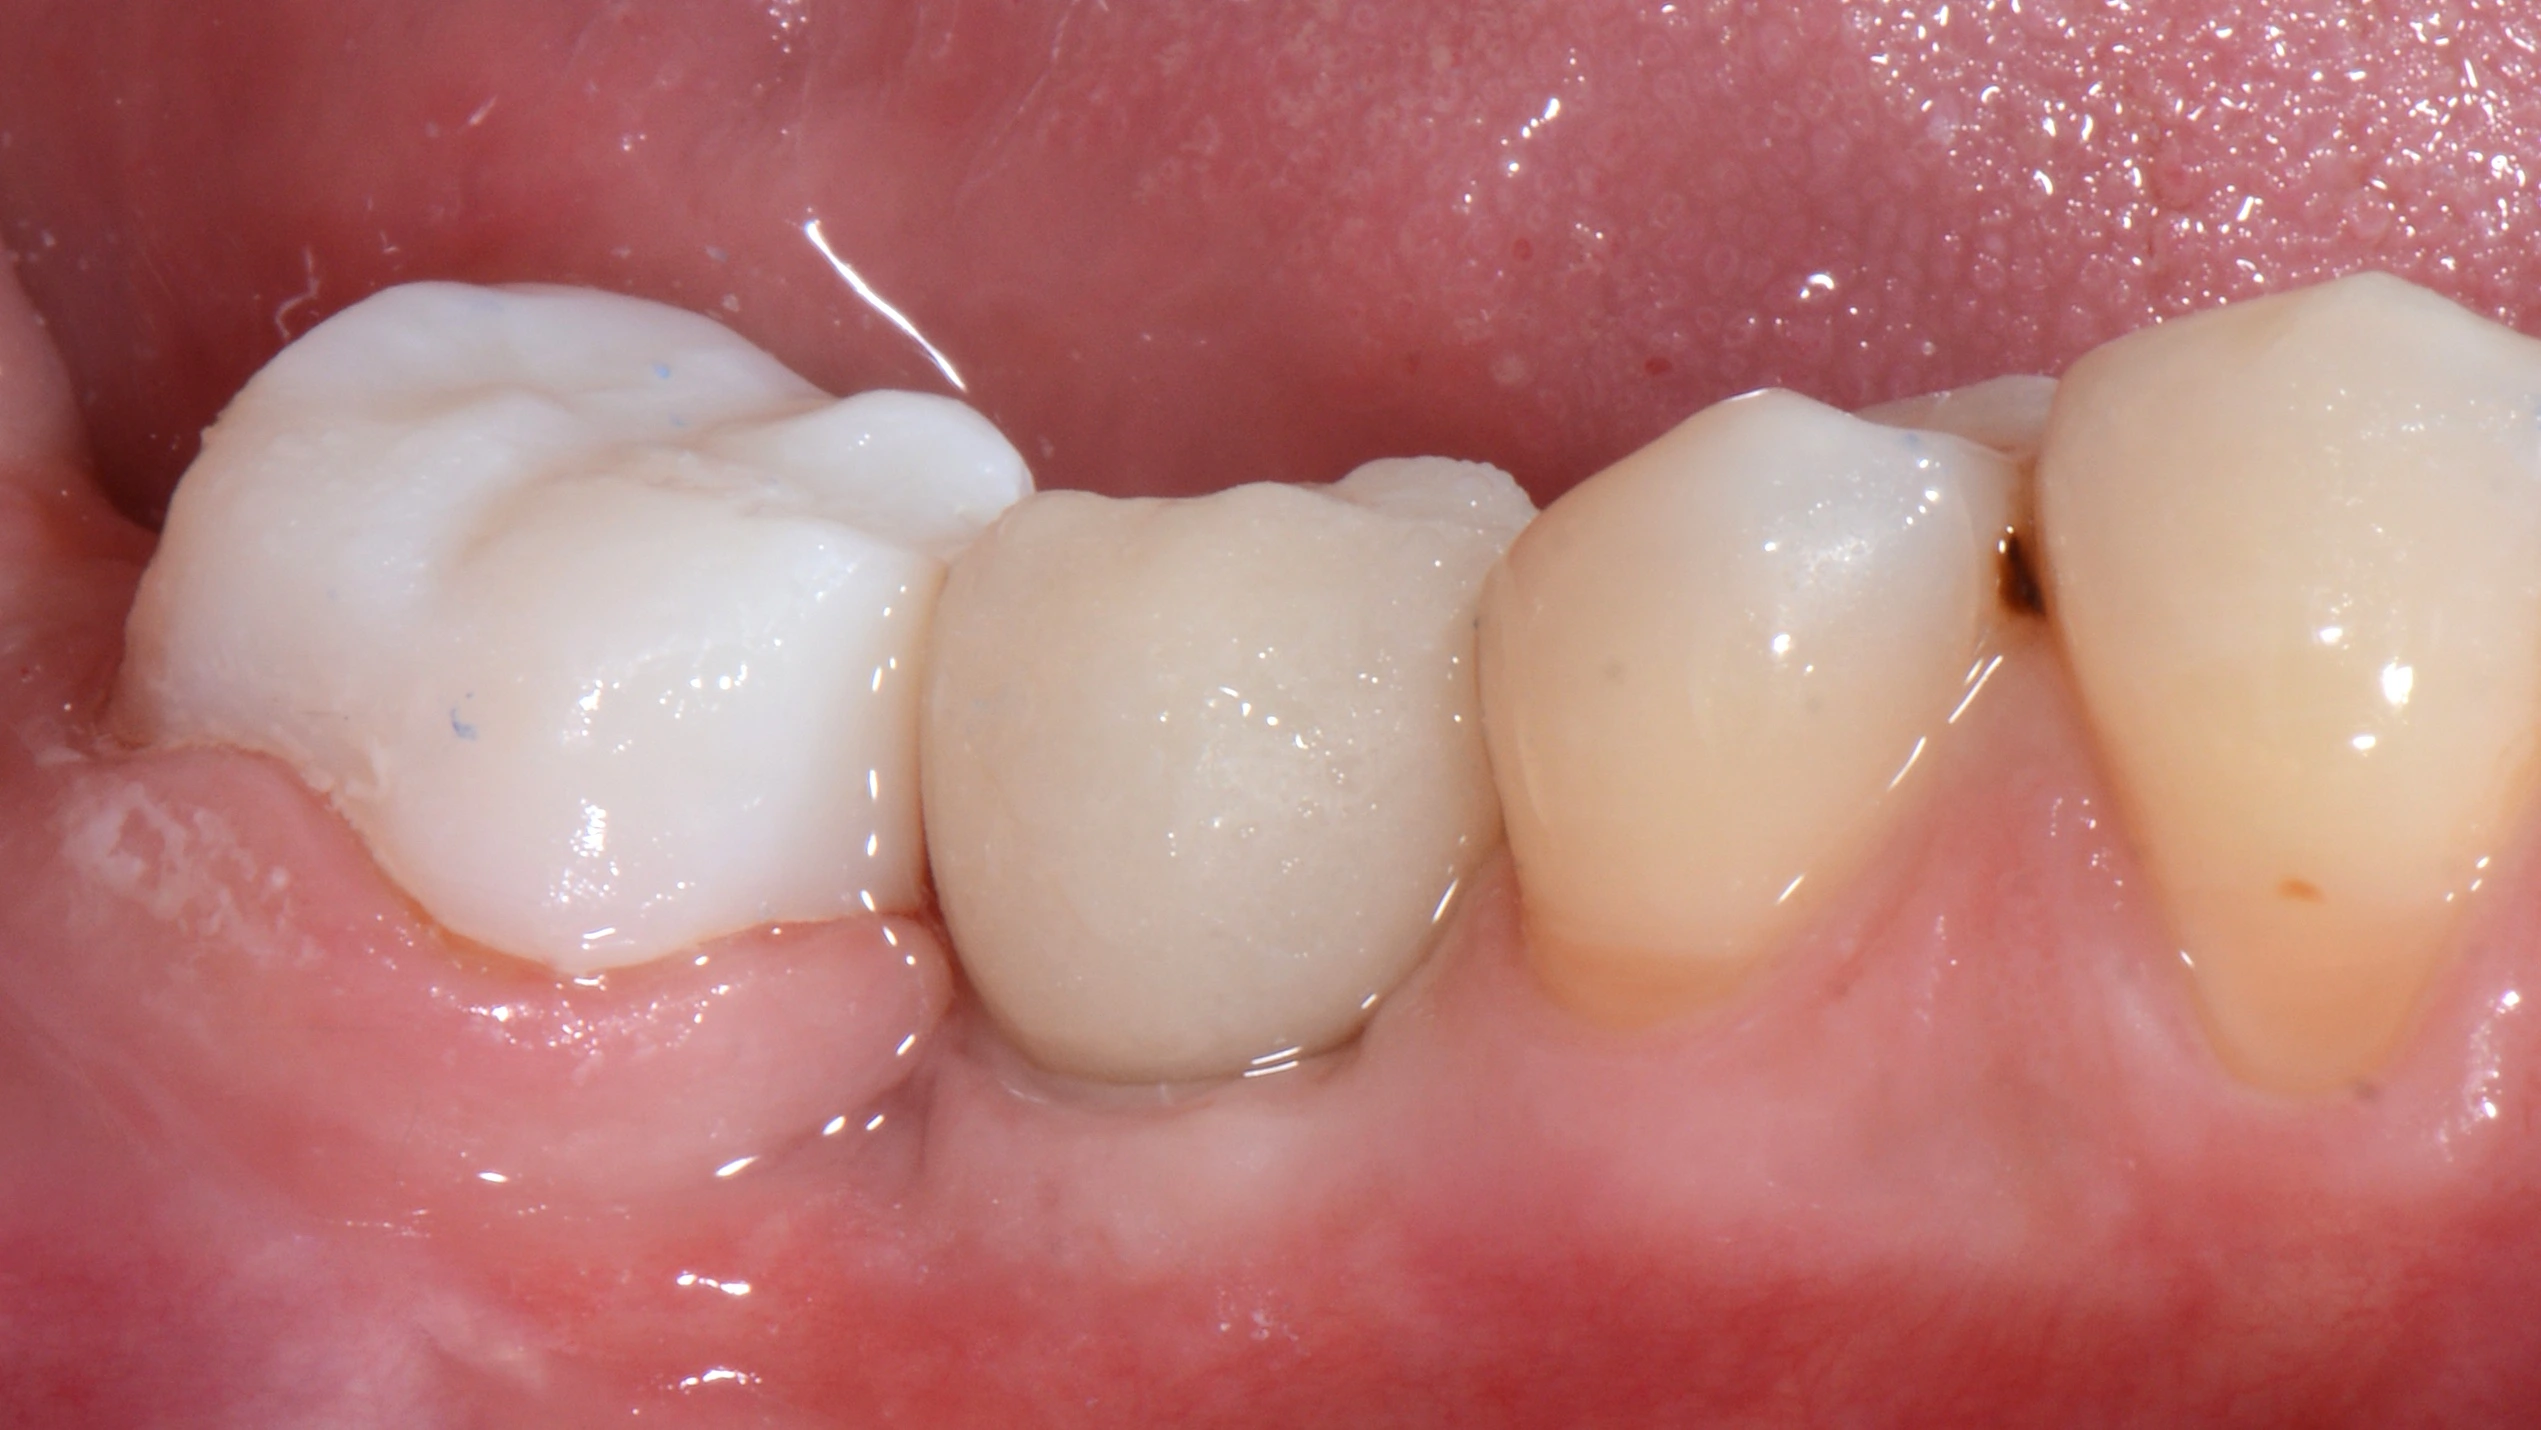

Далее провизорное протезирование с препарированием зуба 47, и после формирования профиля постоянное протеизрование коронками на цементной фиксации на имплантате и на зубе. Зачастую, не всегда вижу необходимость в апрайте семерок, особенно, если в дальнейшем их еще и требуется покрыть коронкой.